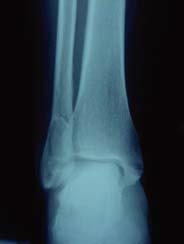

Q

Quel est le diagnostic concernant la fracture de cheville sur cette radio? Quel est le mécanisme lésionnel probable?

A

Fracture bimalléolaire de cheville sus-tuberculaire

mécanisme en aBduction forcée